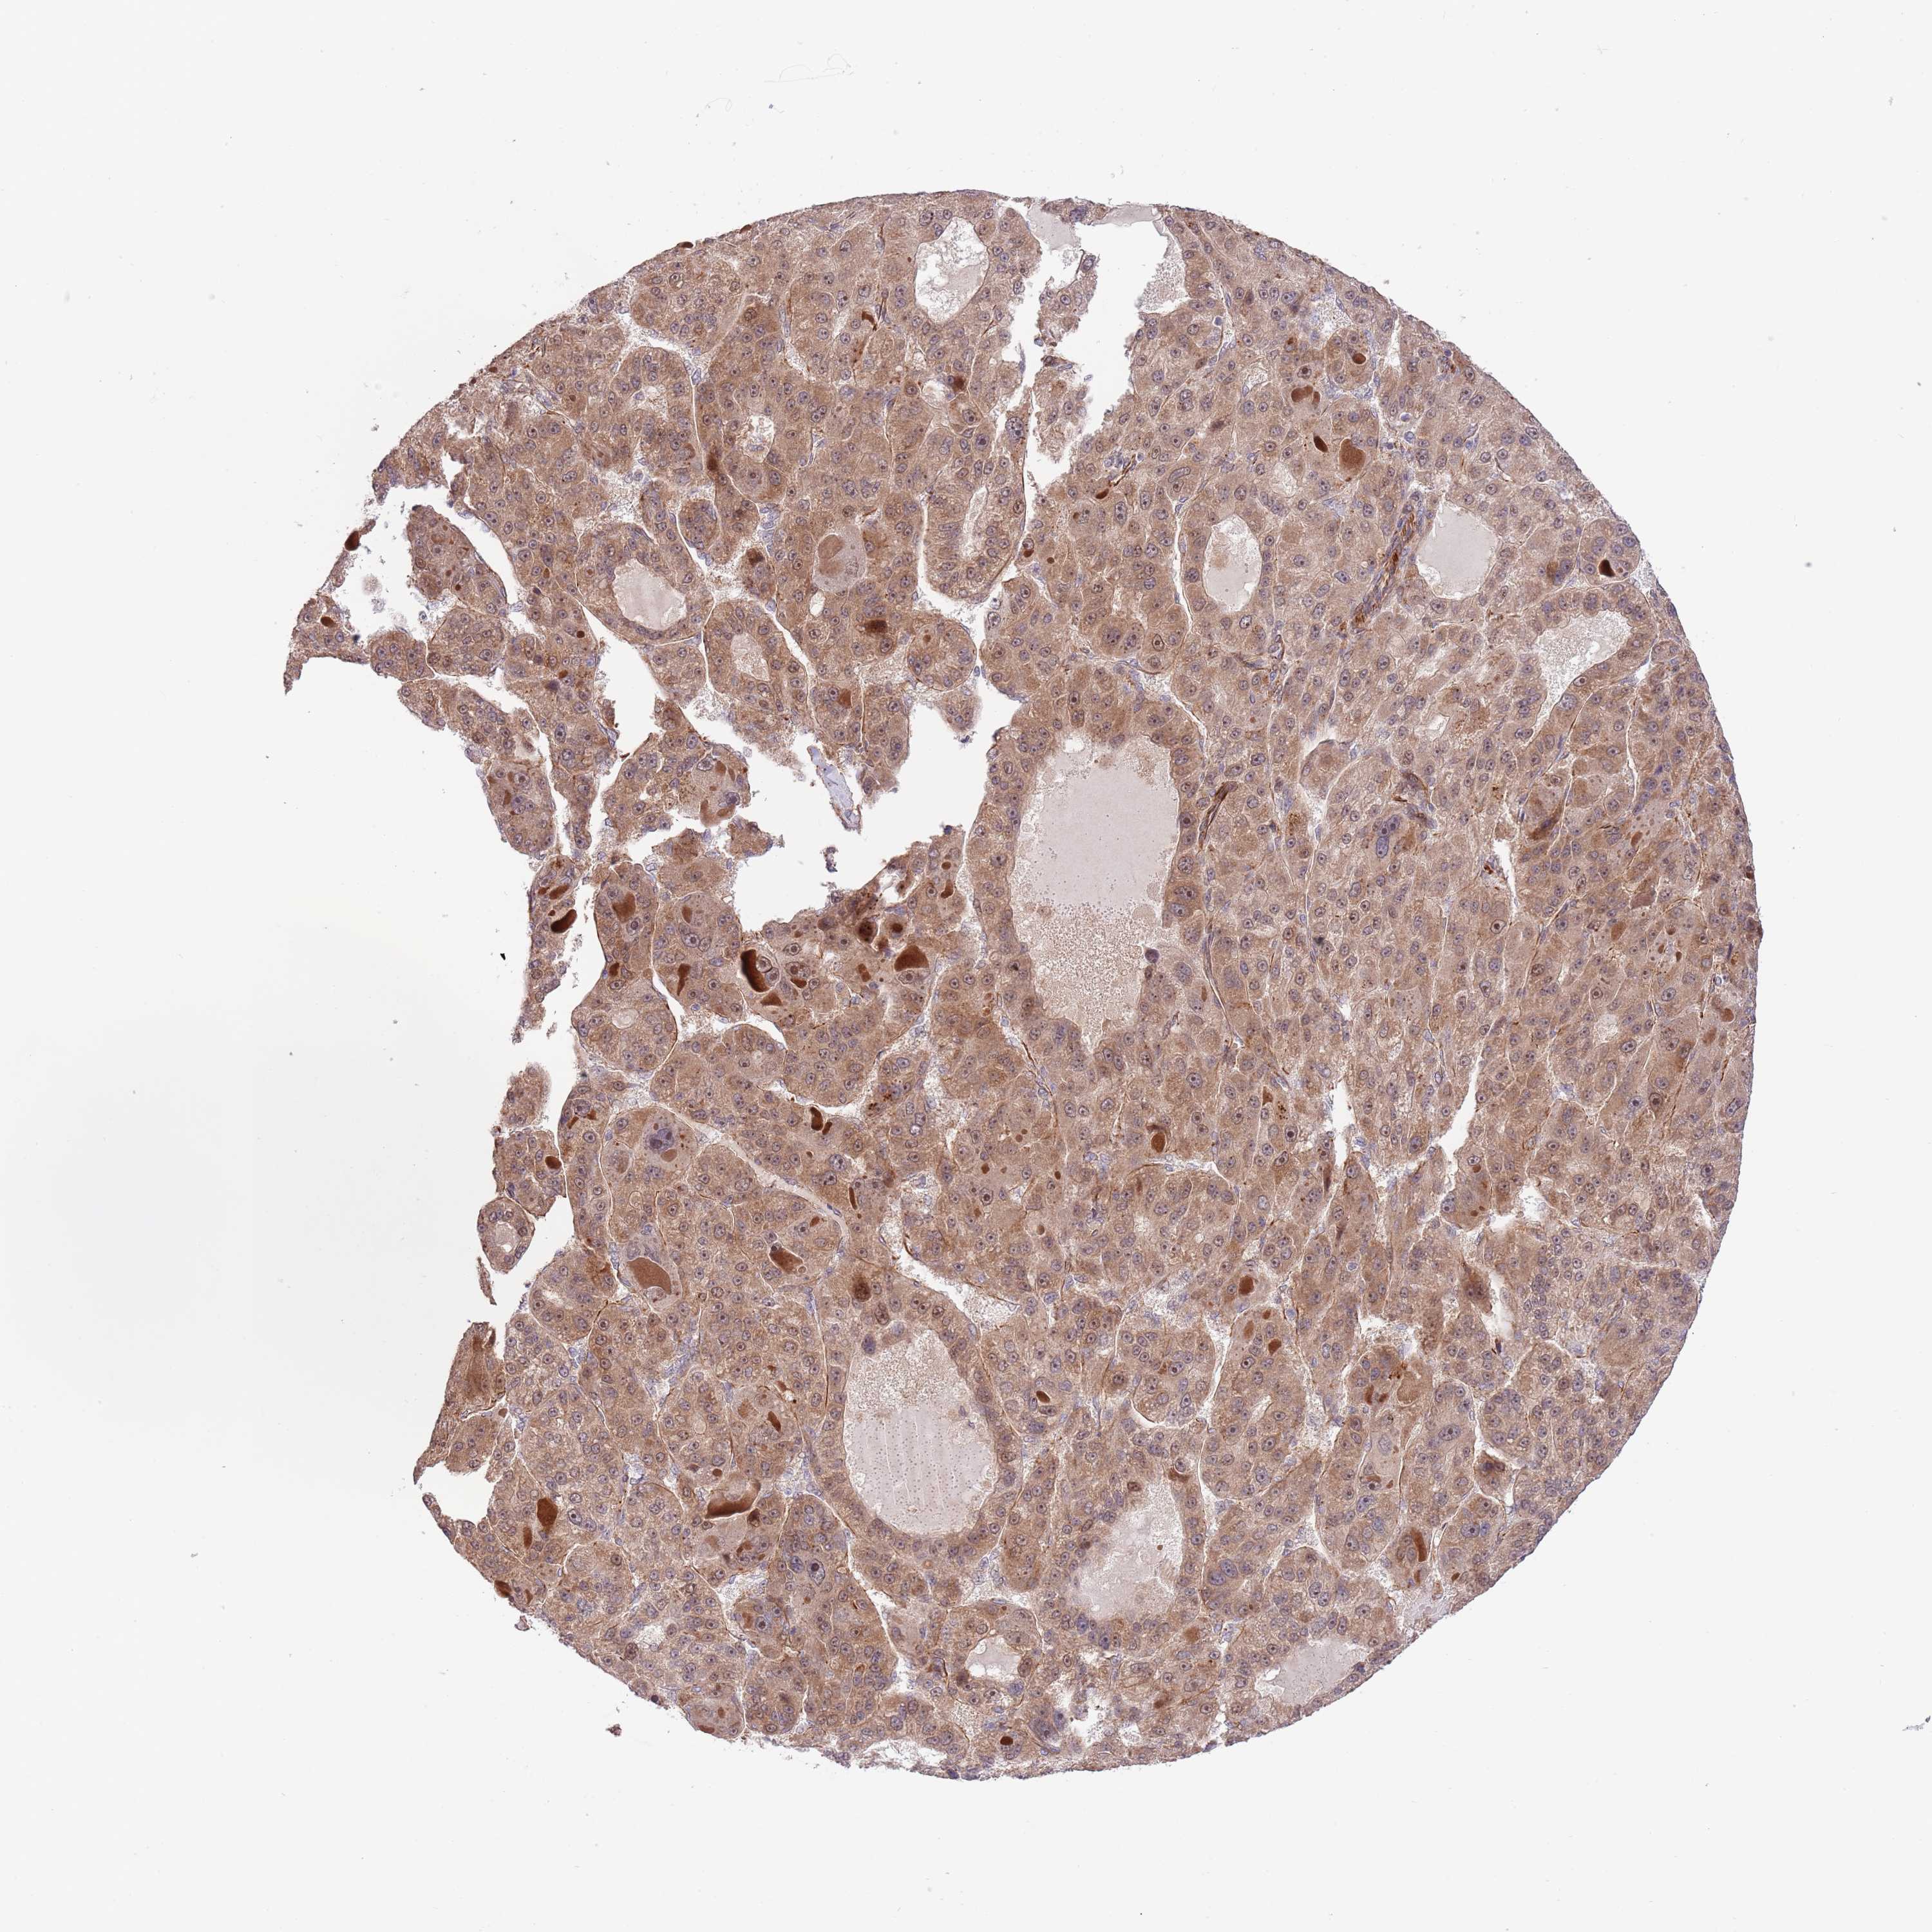

LIVER CANCER - Protein expressioni

A mouse-over function shows sample information and annotation data. Click on an image to view it in a full screen mode. Samples can be filtered based on level of antibody staining by selecting one or several of the following categories: high, medium, low and not detected. The assay and annotation is described here.

Note that samples used for immunohistochemistry by the Human Protein Atlas do not correspond to samples in the TCGA dataset.

Antibody stainingi

Antibody staining in the annotated cell types in the current human tissue is reported as not detected, low, medium, or high, based on conventional immunohistochemistry profiling in selected tissues. This score is based on the combination of the staining intensity and fraction of stained cells.

Each image is clickable and will lead to virtual microscopy that enables deeper exploration of all samples and also displays staining intensity scores, fraction scores and subcellular localization as well as patient and tissue information for each sample.

Antibody HPA019062

Antibody HPA043230

Staining

High

Medium

Low

Not detected

Intensity

Strong

Moderate

Weak

Negative

Quantity

>75%

75%-25%

<25%

None

Location

Nuclear

Cytoplasmic/membranous

Cytoplasmic/membranous,nuclear

Cholangiocarcinoma

Carcinoma, Hepatocellular, NOS